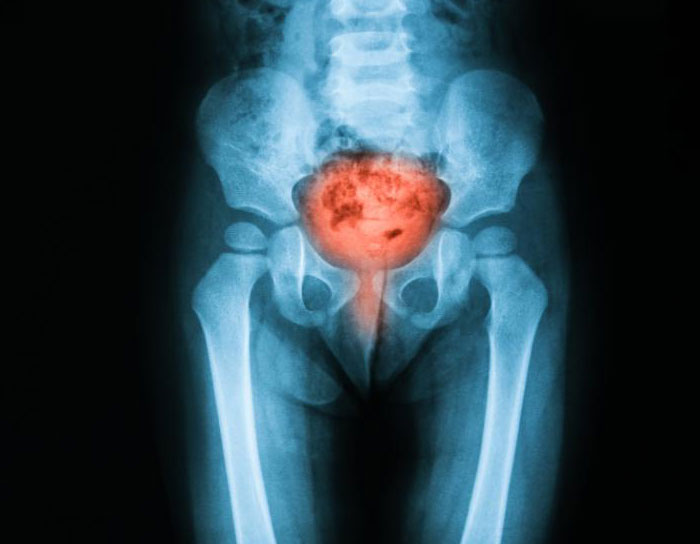

Bildgebender Test

Bildgebende Verfahren sind nicht oft notwendig, können aber bei der Diagnose von Blasenentzündungen hilfreich sein. Ein Röntgenbild oder Ultraschall kann helfen, andere Ursachen der Blasenentzündung auszuschließen, wie z.B. ein strukturelles Problem oder einen Tumor.